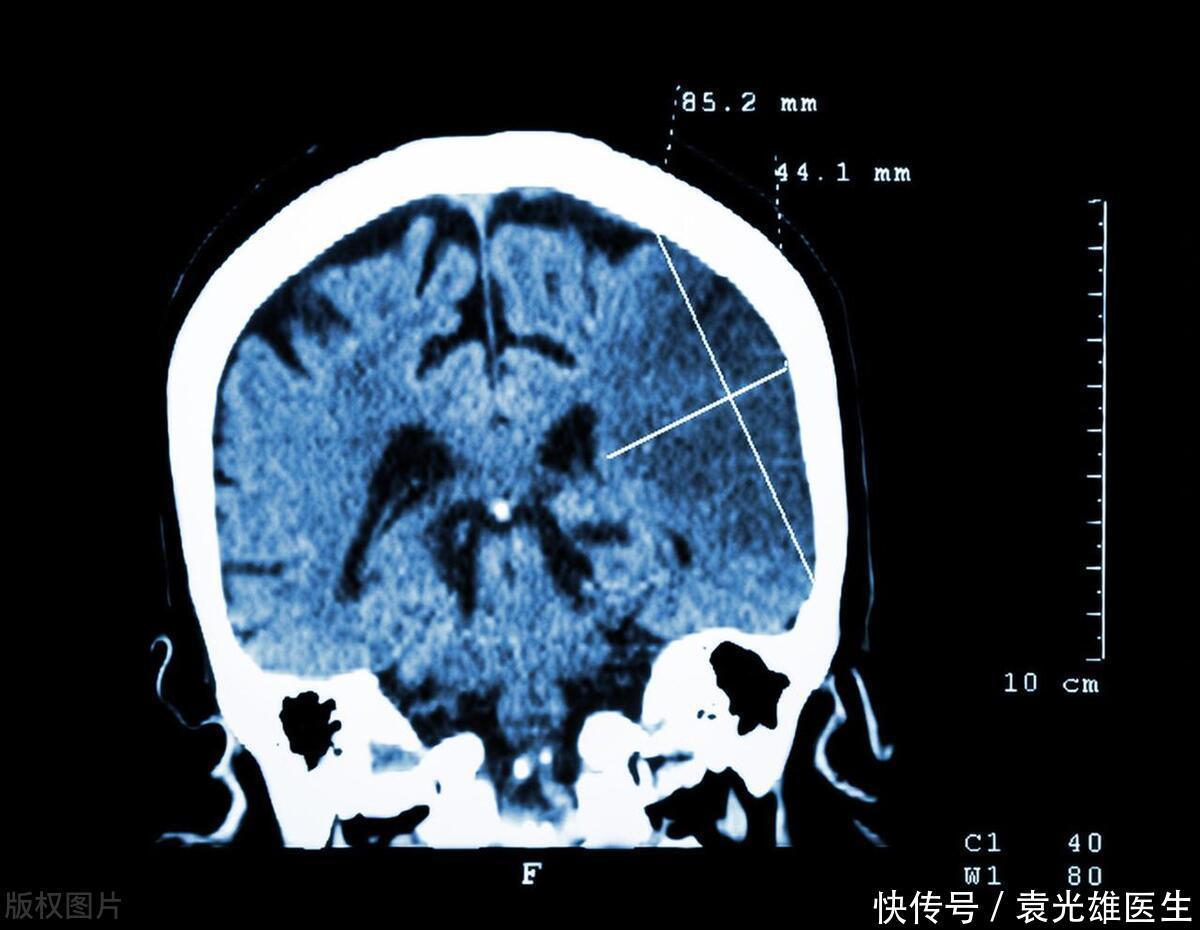

越来越多人突发脑梗,劝告:无论老少,3种食物会增加脑梗发病率